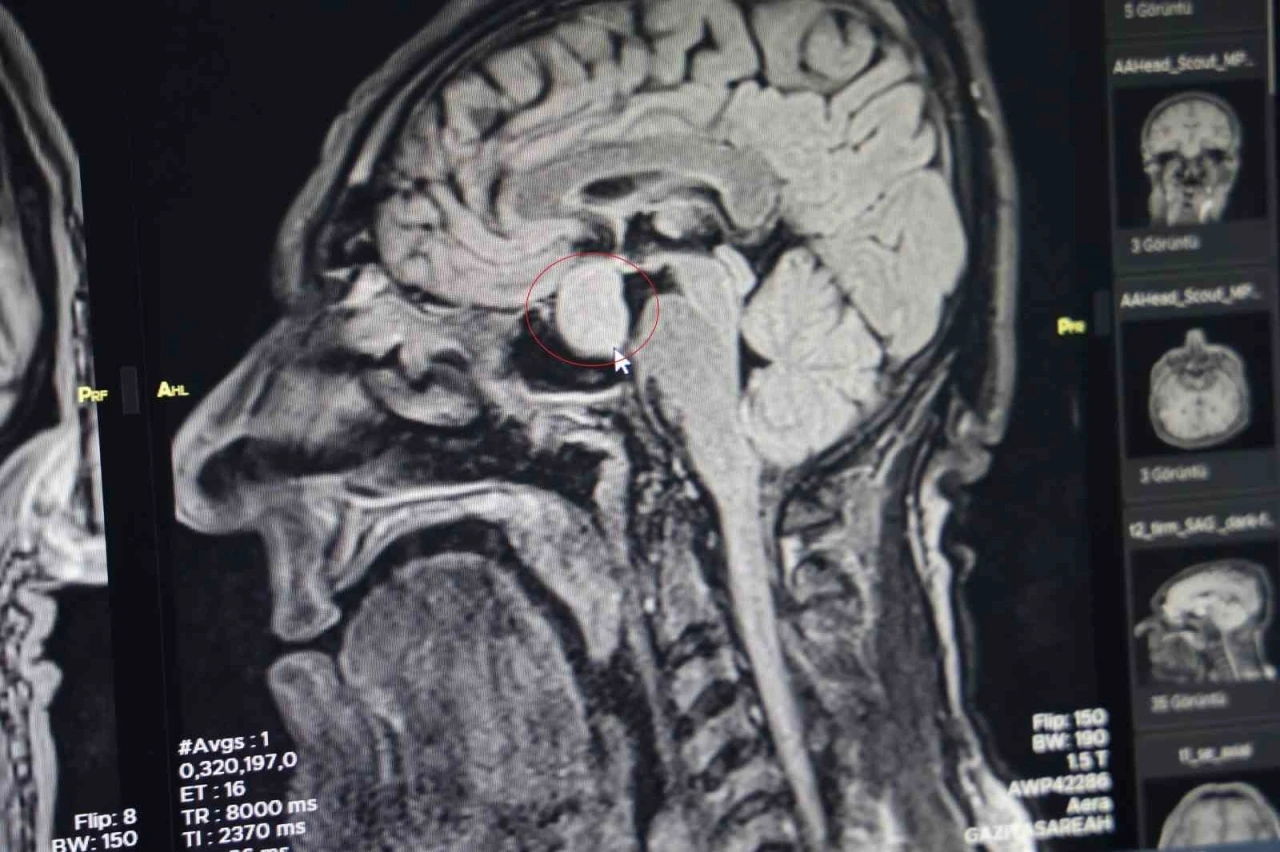

Diyarbakır Gazi Yaşargil Eğitim ve Araştırma Hastanesi, Beyin Cerrahi Bölümü'nde büyük bir başarıya imza atarak, ilk kez kapalı yöntemle beyindeki bir tümörü aldı. Bu yöntemle, 56 yaşındaki bir erkek hastanın beynindeki hipofiz tümörü başarılı bir şekilde çıkarıldı. Ameliyat, yaklaşık 2,5 saat sürdü ve komplikasyon yaşanmadan tamamlandı. Bu gelişme, bölge hastanesi olarak Gazi Yaşargil Eğitim ve Araştırma Hastanesi için bir ilki oluşturuyor.

Hastanın başvurusu, burun kökü ve dilinde kabalaşma, ses kalınlığı gibi şikayetlerle oldu. Yapılan tetkikler sonucunda, dış merkezlerde çekilen MR’larda hipofiz bölgesinde bir iyi huylu tümör tespit edildi. Bu nedenle hasta, hastaneye başvurdu. Beyin Cerrahi Bölümü’nde yapılan tetkiklerin ardından, hastanın büyüme hormonlarının yüksek olduğu belirlendi ve kapalı yöntemle hipofiz tümörü başarıyla alındı.

Doç. Dr. Abdurrahman Çetin, hastayı ameliyat öncesinde bilgilendirdiklerini ve operasyonun çok başarılı geçtiğini belirtti. "Hastanemizde ilk defa burundan kapalı yöntemle girilerek hipofiz tümörüne müdahale ettik. Allah’a şükür, sağ salim bir şekilde tümörü aldık. Operasyonumuz 2-2,5 saat sürdü ve herhangi bir komplikasyon gelişmeden başarılı bir şekilde tamamladık" diyerek, hastanın hızlı bir şekilde iyileştiğini belirtti. İki gün sonra hastanın taburcu edilmesi sağlandı.